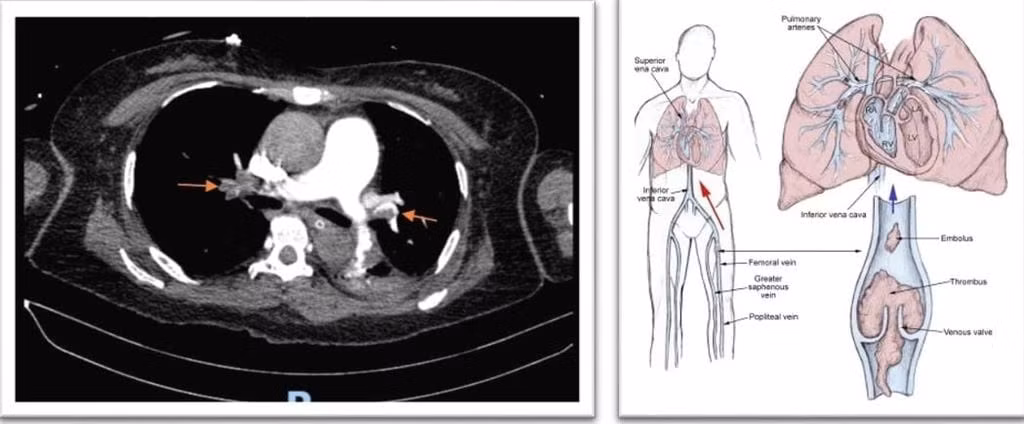

Các nguyên nhân ngưng tim được khảo sát khẩn cấp, kết quả CT-scan ngực người bệnh bị ngừng tuần hoàn hô hấp do thuyên tắc phổi cấp nguy cơ cao, mà nguyên nhân là do các cục huyết khối từ hệ tĩnh mạch sâu ở chân trôi lên gây bít tắc hoàn toàn 2 bên động mạch phổi, một bệnh lý ít gặp nhưng cực kỳ nguy hiểm có thể dẫn tới tử vong ngay lập tức nếu không được xử trí kịp thời.

Siêu âm mạch máu ghi nhận có huyết khối ở tĩnh mạch sâu chân trái, là căn nguyên gây ra tình trạng này.

Kết quả CT-scan khẳng định thuyên tắc phổi cấp, do huyết khối từ tĩnh mạch sâu chân (T) di chuyển lên - Ảnh BVCC